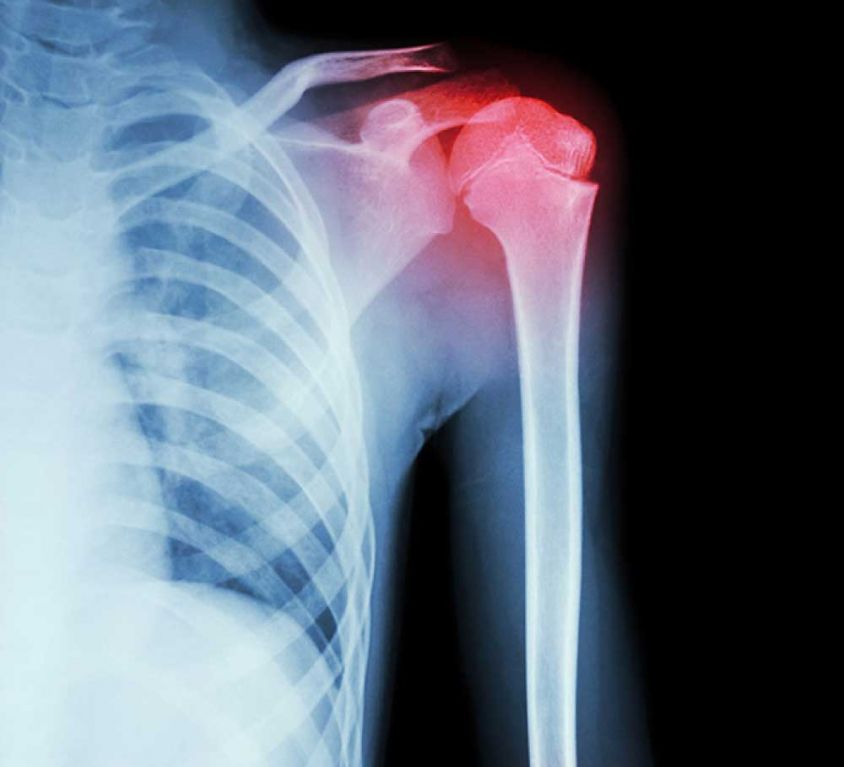

Shoulder and Elbow Procedures

Shoulder and elbow joints allow us to bend, flex, reach, and rotate our arms. However, repetitive overhead movements that are common to some sports and jobs frequently overstress the elbow and shoulder joints resulting in injury. When problems related to tendon tears, instability, fractures, arthritis and other conditions impede movement, both surgical and non-surgical treatments are considered to ease pain and help restore movement.